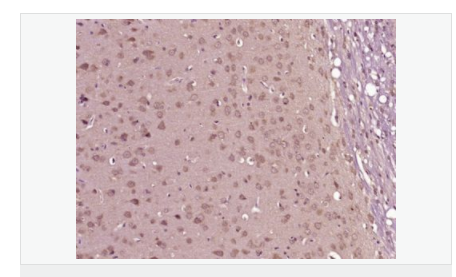

| 產品應用 | WB=1:500-2000 IHC-P=1:100-500 IHC-F=1:100-500 ICC=1:100-500 IF=1:100-500 (石蠟切片需做抗原修復) not yet tested in other applications. optimal dilutions/concentrations should be determined by the end user. |

| 產品介紹 | This gene encodes the epsilon member of the sarcoglycan family. Sarcoglycans are transmembrane proteins that are components of the dystrophin-glycoprotein complex, which link the actin cytoskeleton to the extracellular matrix. Unlike other family members which are predominantly expressed in striated muscle, the epsilon sarcoglycan is more broadly expressed. Mutations in this gene are associated with myoclonus-dystonia syndrome. This gene is imprinted, with preferential expression from the paternal allele. Alternatively spliced transcript variants encoding different isoforms have been found for this gene.[provided by RefSeq, Oct 2010] Function: Component of the sarcoglycan complex, a subcomplex of the dystrophin-glycoprotein complex which forms a link between the F-actin cytoskeleton and the extracellular matrix. Subcellular Location: Cell membrane > sarcolemma. Cytoplasm > cytoskeleton. Tissue Specificity: Ubiquitous. DISEASE: Defects in SGCE are a cause of dystonia type 11 (DYT11) [MIM:159900]; also known as myoclonic dystonia or alcohol-responsive dystonia. DYT11 is a myoclonic dystonia. Dystonia is defined by the presence of sustained involuntary muscle contractions, often leading to abnormal postures. DYT11 is characterized by involuntary lightning jerks and dystonic movements and postures alleviated by alcohol. Inheritance is autosomal dominant. The age of onset, pattern of body involvement, presence of myoclonus and response to alcohol are all variable. Similarity: Belongs to the sarcoglycan alpha/epsilon family. SWISS: O43556 Gene ID: 8910 Database links: Entrez Gene: 8910 Human Entrez Gene: 20392 Mouse Omim: 604149 Human SwissProt: O43556 Human SwissProt: O70258 Mouse Unigene: 371199 Human Unigene: 8739 Mouse Unigene: 185815 Rat Important Note: This product as supplied is intended for research use only, not for use in human, therapeutic or diagnostic applications. |